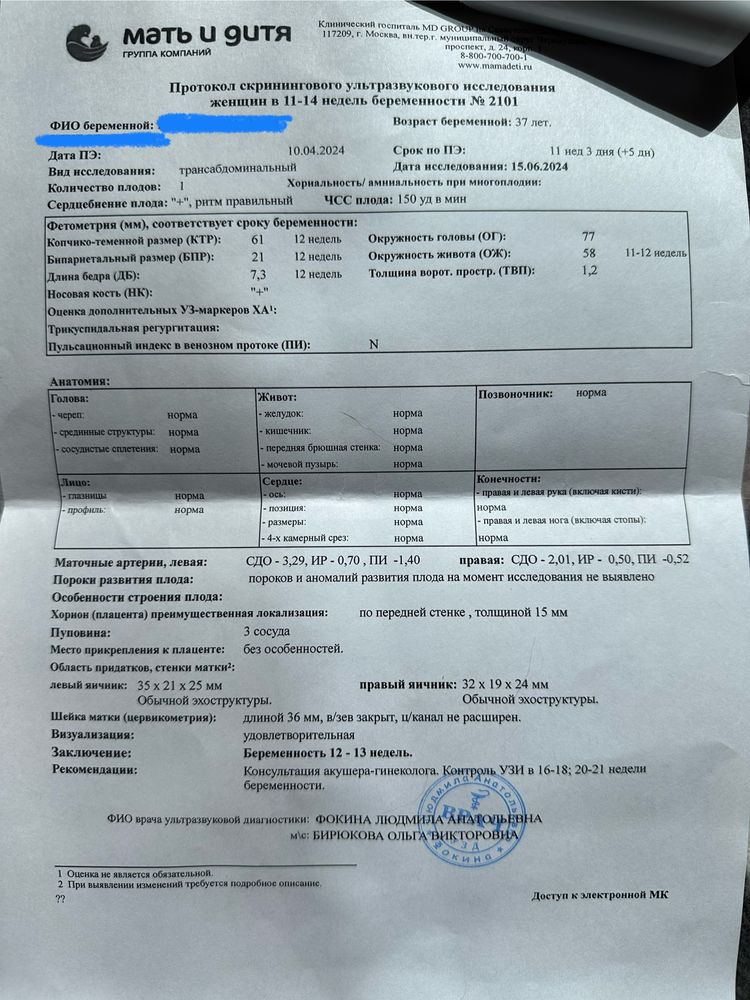

По результатам УЗИ все прекрасно. Сдала кровь,но тут результаты будут недели через две. Но мне и не к спеху,особого волнения,как оказалось,я не испытываю.

По итогу жду результаты крови. Посмотрим какие там риски.

Они за неделю делают кровь. Даже меньше по моему ))